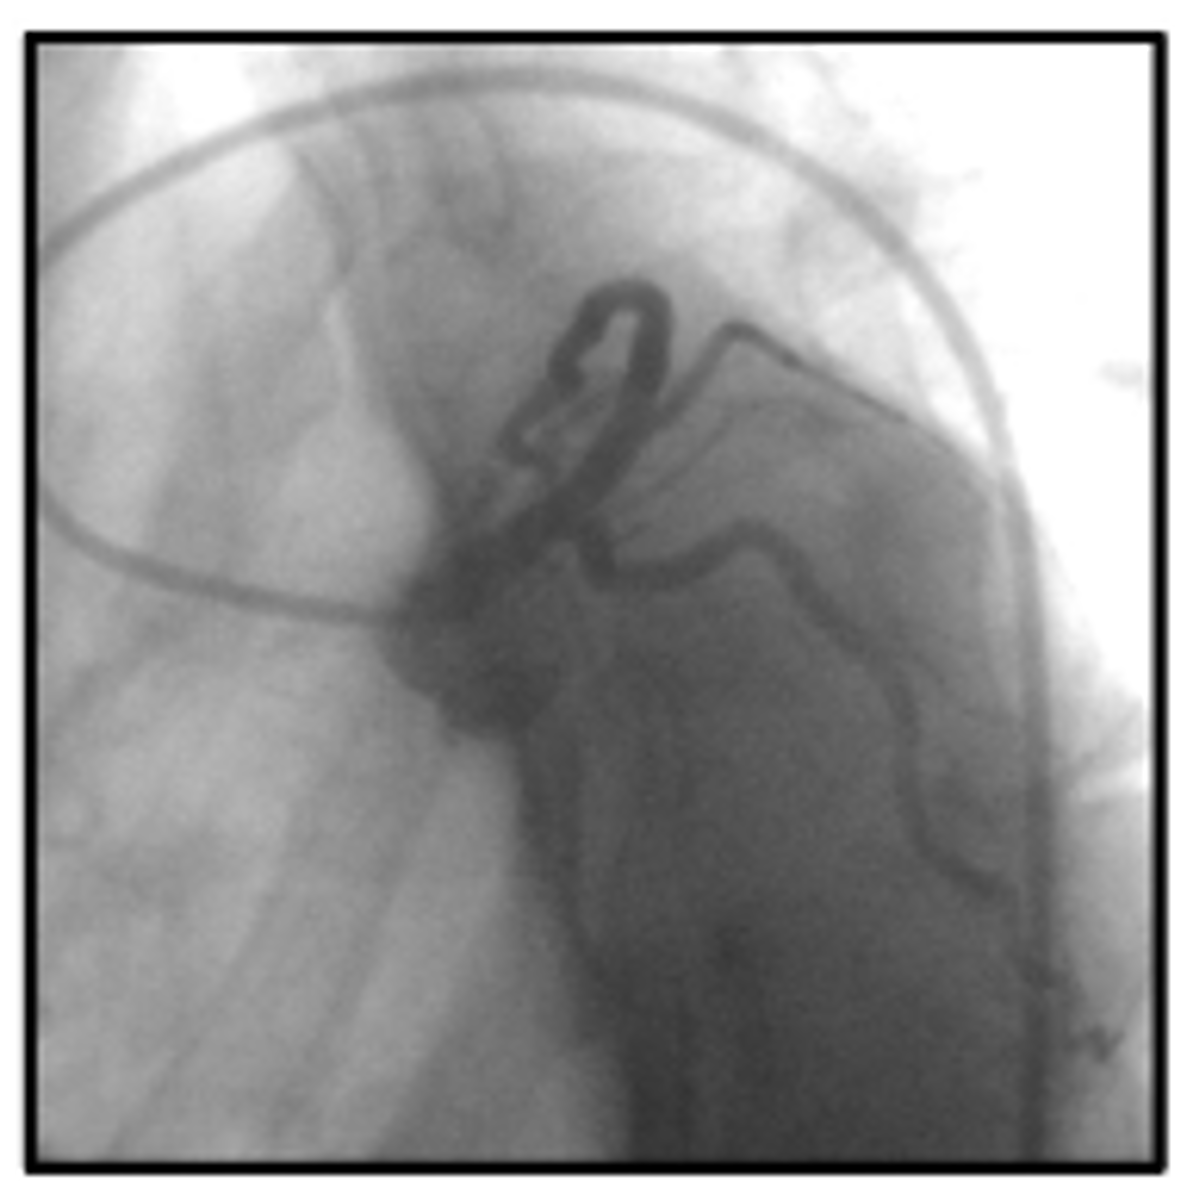

RAO

RCA looks like an L, what view

LAO

RCA looks like an C, what view